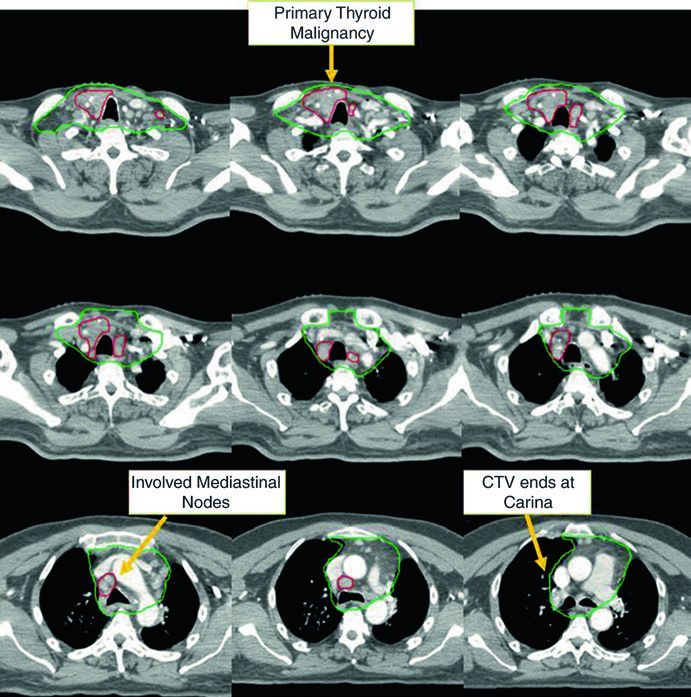

Doença Pouco Diferenciada e Omissão do Pescoço Lateral

Nem todos os casos exigem irradiação bilateral do pescoço lateral. O último caso do capítulo demonstra um cenário em que a omissão do pescoço lateral foi deliberada e clinicamente justificada, ilustrando o princípio de individualização baseada no padrão de recorrência do paciente.

Caso 5 — Câncer pouco diferenciado, fenótipo folicular (Fig. 9.5): Mulher de 69 anos com câncer de tireoide pouco diferenciado de fenótipo folicular, aderido a traqueia e esôfago, submetida a ressecção e iodo radioativo, que recorreu com massa paratraqueal direita invadindo a traqueia. Após nova ressecção e esvaziamento cervical, recebeu quimiorradiação adjuvante. O CTV60 Gy (verde) cobre o compartimento central e o mediastino superior. O tratamento do pescoço lateral foi omitido, dada a alta probabilidade de recorrência no compartimento central — a dose e o risco foram priorizados onde o benefício clínico era máximo.

A decisão de omitir o pescoço lateral não é trivial. Ela pressupõe que o risco de recorrência lateral é suficientemente baixo para que a redução de toxicidade justifique a ausência de cobertura. No cenário deste caso — doença central recorrente com esvaziamento cervical recente e sem linfonodos laterais comprometidos — a omissão é razoável e alinhada com o princípio de individualização do tratamento. Omitir o pescoço lateral reduz significativamente o volume irradiado, com benefício direto na preservação da função de deglutição e redução de xerostomia.